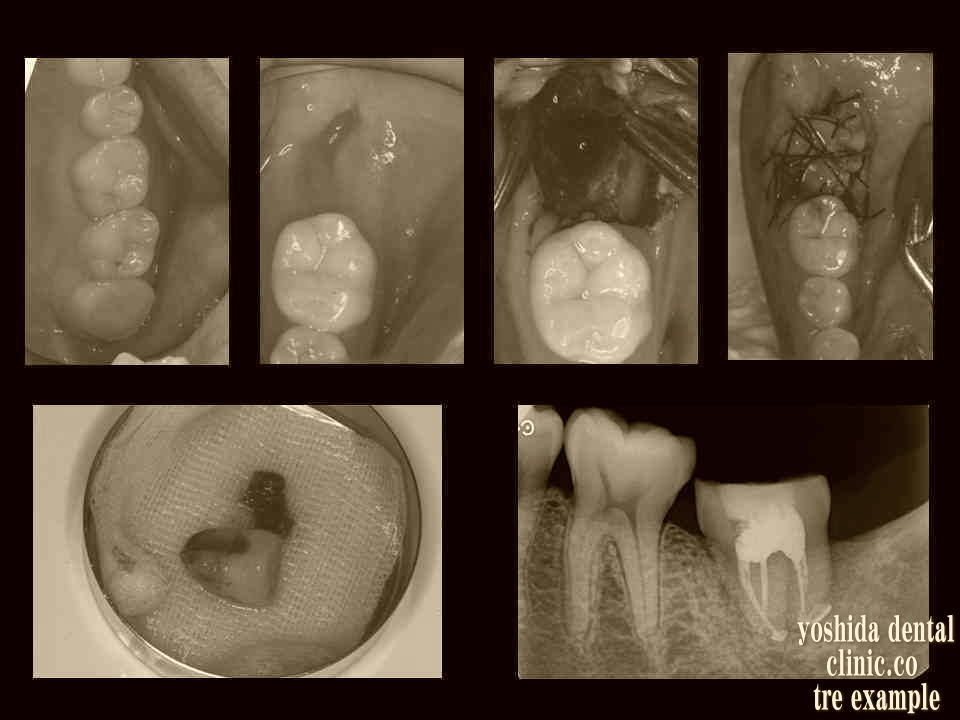

歯牙移植術(保険治療)

歯牙移植  智歯いわゆる親知らずを奥歯に移植できる場合があります。

今回、左下の臼歯が根吸収を起こしていて保存できないため、左上の智歯を下の抜歯予定部位へ移植しました。

歯牙移植レシピエントサイトの抜歯   左下の臼歯を智歯と共に抜歯して、抜歯した歯の根吸収を確認。

R→

歯牙移植術ドナーサイトからレシピエントサイトへ   左上の智歯を下部に移植しました。

歯牙移植歯生着後の補綴 親しらずは移植され、安定して噛めておられます。